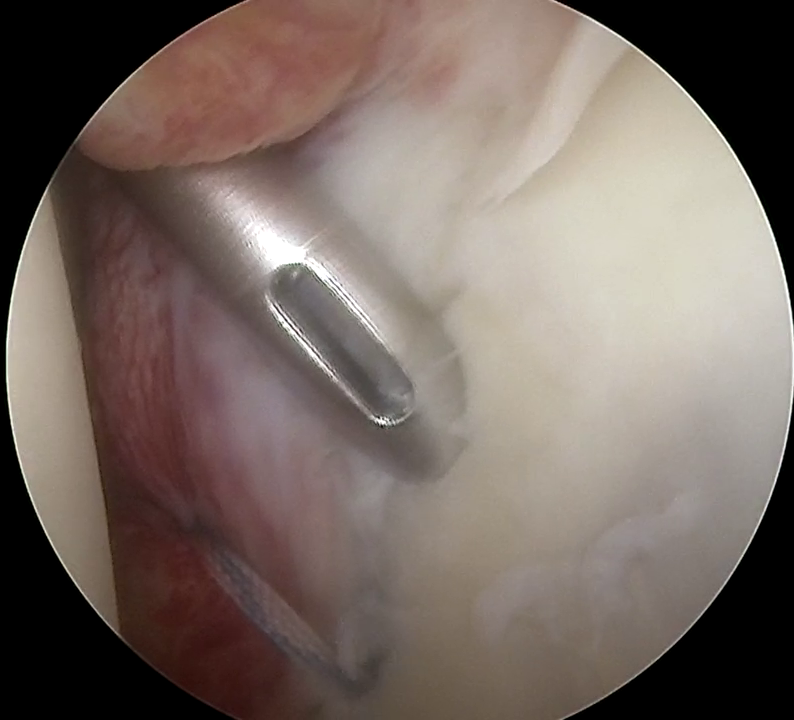

Shoulder Arthroscopy.

Shoulder arthroscopy is a modern, minimally invasive technique that has evolved into a primary method for addressing numerous orthopedic conditions, often replacing the need for open surgery. Initially, it was used exclusively for diagnostic purposes, allowing the physician to obtain a clear view of the joint from the inside.

Shoulder conditions and injuries treated arthroscopically:

- Rotator cuff tear (supraspinatus, infraspinatus, subscapularis tendons)

- Calcific tendinitis.

- Shoulder stiffness or "frozen shoulder."

- Injuries and disorders of the acromioclavicular joint.

- Instability and labral tear.

- Subacromial impingement syndrome.

- Lesions of the long head of the biceps tendon.

- Articular cartilage lesions.

- Intra-articular fractures and loose bodies.

- Early stages of arthritis.

- Synovial membrane disorders

- Suprascapular nerve entrapment.